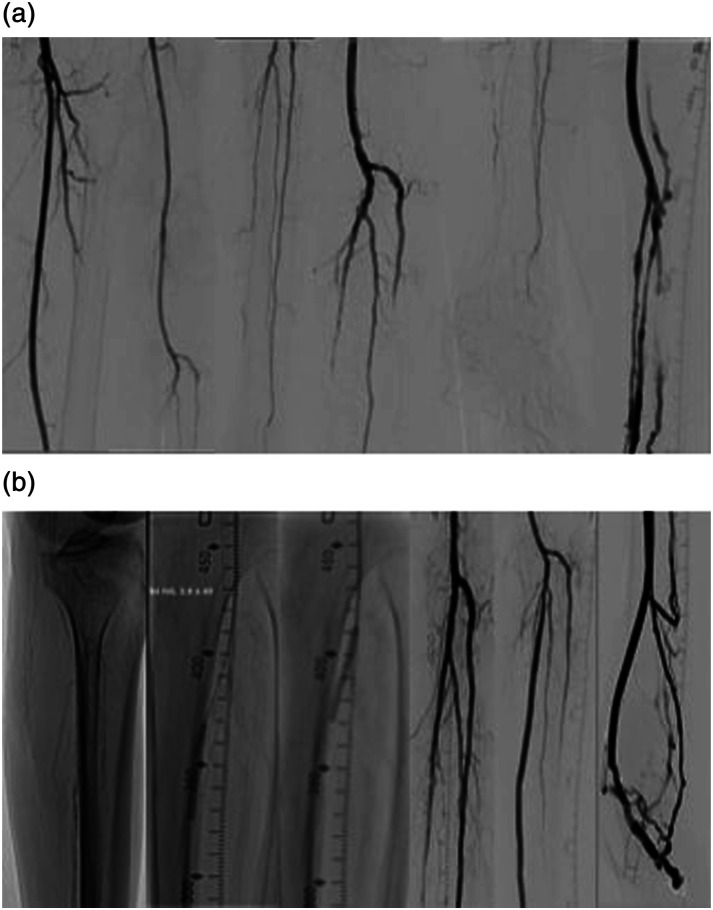

目的:报告首例接受血管内碎石术(IVL)辅助经皮深静脉动脉化术(pDVA)的慢性肢体缺血(CLTI)患者:病例报告 1:一名 81 岁的患者因腘动脉和胫骨主干(TPT)严重钙化病变、胫骨远端和足弓闭塞而出现 CLTI。患者接受了 IVL 和腘动脉远端及 TPT 的药物涂层球囊血管成形术,以在 pDVA 之前改善血流。病例报告 2:一名 64 岁的患者左侧肢体静息痛,伴有单血管胫腓动脉栓塞和足弓闭塞,患者接受了 3.5 mm IVL 治疗,随后如上所述成功进行了 pDVA。在胫后动脉近端进行了 IVL,以优化回路的流入量,并改变从动脉到静脉系统交叉点的顺应性。患者在指数手术后 5 个月再次接受了足底静脉弓血管成形术,此后 2 年的随访中一直没有症状:结论:联合使用 IVL 和 pDVA 可以改善重建的通畅性,对无选择 CTLI 患者有临床益处。

PurposeTo report the first chronic limb-threatening ischemia (CLTI) patients who underwent an intravascular lithotripsy (IVL)-assisted percutaneous deep vein arterialization (pDVA).Case Report 1An 81-year-old patient presented with CLTI and a heavily calcified lesion of the popliteal artery and tibioperoneal trunk (TPT), with a distal tibial and foot arch occlusion. The patient underwent IVL and drug-coated balloon angioplasty for the distal popliteal artery and of the TPT to improve the inflow prior to pDVA. The wound situation remained stable without secondary procedure until the patient`s deaths due to complications of urosepsis 3 months later.Case Report 2A 64-year-old patient with rest pain of the left limb with a single-vessel tibial run-off (peroneal artery) and occluded pedal arch was treated with 3.5 mm IVL followed by a successful pDVA as mentioned above. IVL performed in the proximal posterior tibial artery to optimize the inflow to the circuit and change the compliance of the crossing point from the arterial to the vein system. The patient underwent repeat angioplasty of the plantar vein arch 5 months after the index procedure and thereafter remained asymptomatic during 2 years of follow-up.ConclusionThe combined use of IVL and pDVA could improve the patency of the reconstruction with clinical benefits in no-option CTLI patients.